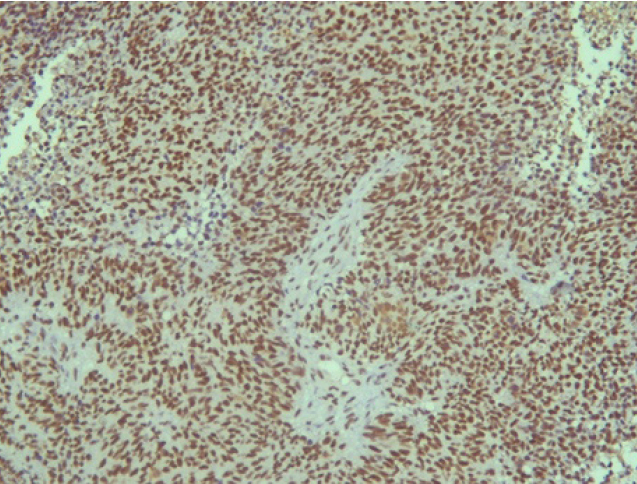

Опухоль с одинаковой частотой локализовалась в правой и левой половинах носа. Но из-за близости соседних анатомических структур и особенностей местнодеструирующего роста опухоли, у двух пациентов первичный очаг изначально диагностировали интракраниально (22,2 %), у двух – в верхнечелюстной пазухе (22,2 %), у одного – в носоглотке (11,1 %) и у двух пациентов (22,2 %) из-за степени распространенности процесса было невозможно анатомически точно определить область первичного возникновения опухоли. В таких ситуациях единственным способом верификации морфологической принадлежности злокачественного процесса является гистологическое исследование (рис. 1).

Эстезионейробластома по своей гистологической структуре напоминает лимфосаркому или симпатобластому и представлена комплексами гиперхромных клеток со структурами типа ложных розеток и скудным нейрофибриллярным матриксом, выраженным полиморфизмом [3, 6].

Поэтому при первичном гистологическом исследовании диагноз эстезионейробластомы был установлен только у 6 пациентов (66,6 %), у троих больных (33,4 %) были диагностированы другие формы злокачественного процесса, что не соответствовало клиническим проявлениям. Во всех случаях проводили иммуногистохимическое (ИГХ) исследование. ИГХ-исследование проводили на срезах с парафиновых блоков с использованием антител к Keratin.Pan (AE/AE3), CD45 (Cocktail), Synaptophysin (SP11), ChromograninA (SP12), CD56 (56C04), Ki-67 (30-9), p63 (7JUL)RTU, S100, INI1, CD99 (HO36-1.1). Также выполняли доставку с антителами к EMA (E29), TTF1 (8G7G3/1). В диагностических материалах была отмечена положительная экспрессия Synaptophysin, ChromograninA, CD56, Ki-67 (до 90% ядер), INI1 (рис. 2–6).

Рис. 1. Ольфакторная нейрогенная опухоль полости носа (эстезионейробластома, клеточный полиморфизм) ×320 (окраска Г-Э)